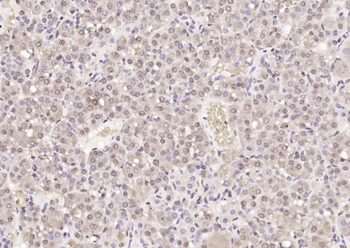

FC, ICC, IF, IHC-Fr, IHC-P, WB

Human, Mouse, Rat

Rat

Rabbit

Recombinant

Unconjugated

200 μl, 50 μl, 100 μl - Featured